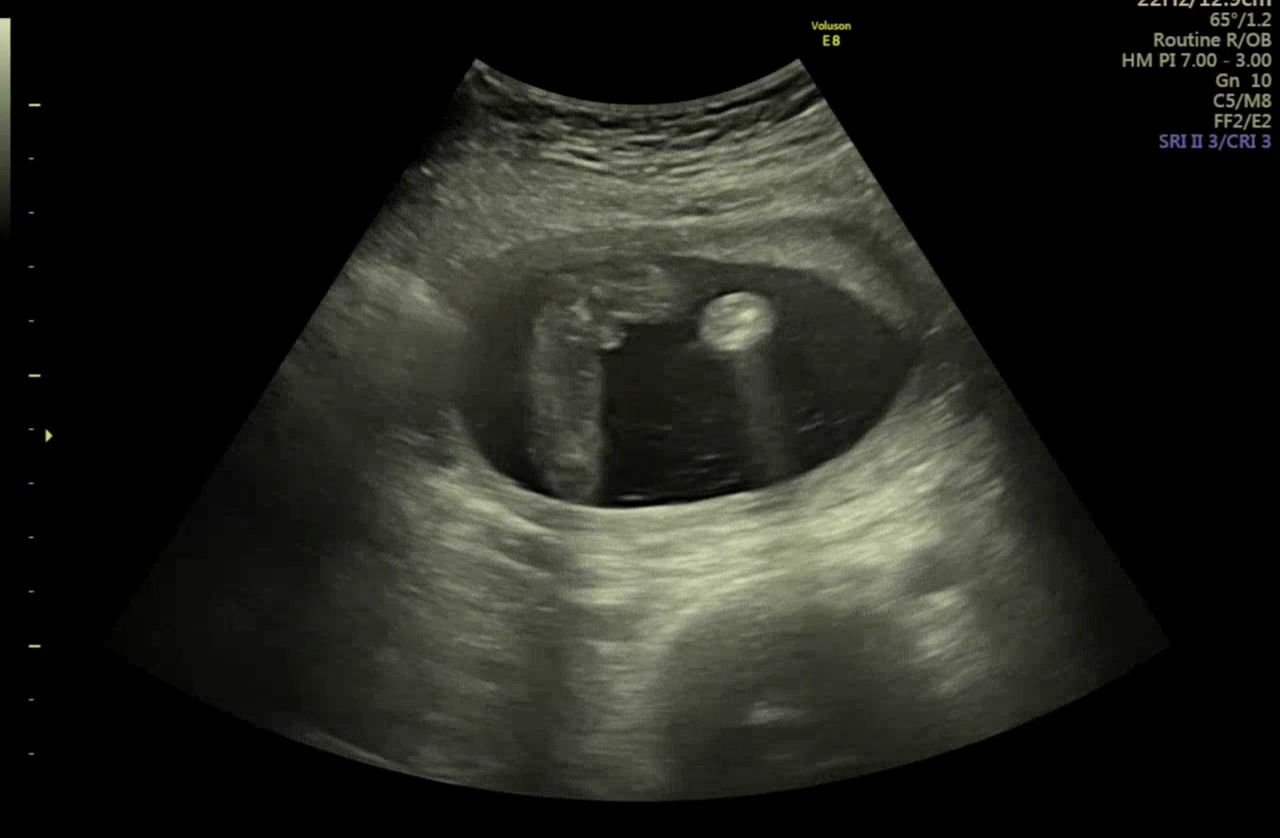

16주 초음파 영상 봐주세요!

병원에서는 딸같다는데 2주전엔 아들같다고해서 헷갈리네요ㅠ 댓글에 추가사진 달게요!

이 사진보면 또 딸같기도해요!ㅠ